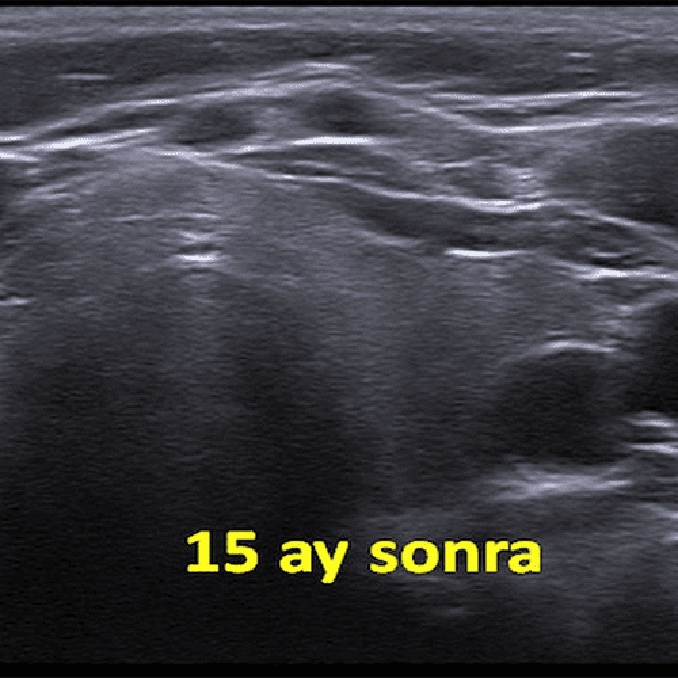

Sol tiroid lobunda rastlantısal olarak saptanan 12 mm çaplı papiller mikrokarsinomu olan 52 yaşındaki kadın hastamızda ultrason eşliğinde perkütan mikrodalga ablasyonu yapıldı. On beş ay sonra, nodül ultrasonda izlenememiştir.